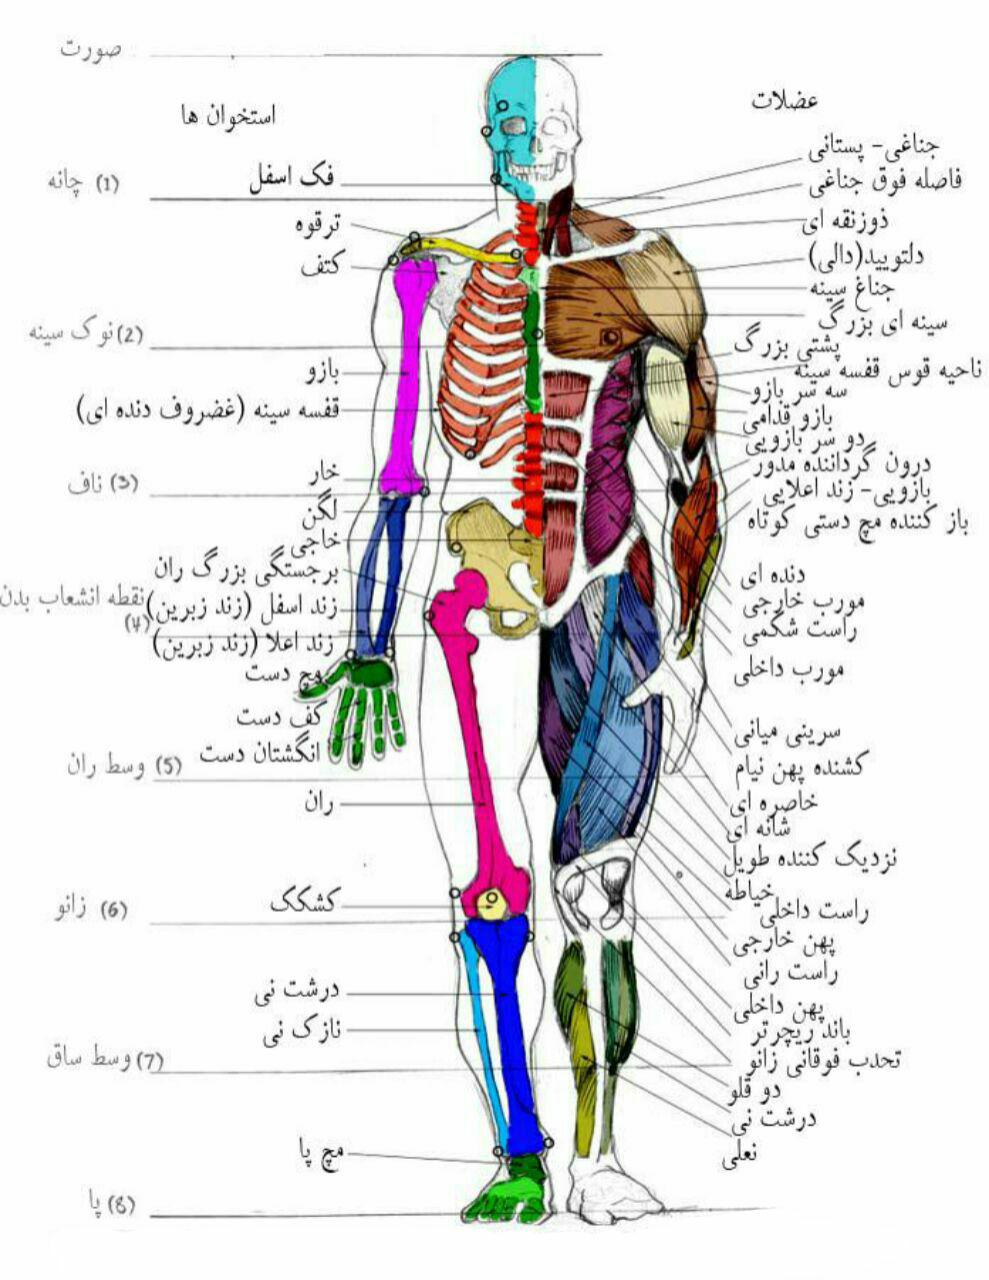

عکس اسکلت بدن انسان. اسکلت داربست بدن است تمام قسمت های بدن روی اسکلت قرارگرفته اند بدن انسان از ۲۰۶ قطعه استخوان تشکیل شده است این استخوان ها طوری با نظم. هر قسمت بدن از انواع مختلف سلول تشکیل شده است. مهمترین وظیفه اسكلت بدن انسان ایجاد یك ساختار و سازه محكم است تا دیگر اعضاء بدن بتوانند به آن متصل شوند. سازه و چهارچوب اصلی بدن.

اسکلت داربست بدن است تمام قسمت های بدن روی اسکلت قرارگرفته اند بدن انسان از ۲۰۶ قطعه استخوان تشکیل شده است این استخوان ها طوری با نظم کنار هم قرار گرفته اند که انسان را قادر می سازد حرکات دقیقی داشته باشد. بدون اسكلت بدن مانند كرم شل و نرم است و این نوع شكل بندی نمیتواند. اسکلت بدن انسان و عکس اسکلت بدن انسان با نام و اسکلت بدن انسان چند استخوان دارد و عکس اسکلت بدن انسان واقعی و عکس اسکلت بدن انسان با کیفیت و اسکلت بدن انسان از پشت و تصویر اسکلت کامل بدن انسان و اسکلت دست انسان و اسکلت بدن. معرفی بدن انسان اسکلیت.

اسکلت داربست بدن است تمام قسمت های بدن روی اسکلت قرارگرفته اند بدن انسان از ۲۰۶ قطعه استخوان تشکیل شده است این استخوان ها طوری با نظم کنار هم قرار گرفته اند که انسان را قادر می سازد حرکات دقیقی داشته باشد. استخوان یک نسج بسیار محکم است زیرا در ترکیب آن منرالها مانند کلسیم و دیگر وجود. اسکلت داربست بدن است تمام قسمت های بدن روی اسکلت قرارگرفته اند بدن انسان از ۲۰۶ قطعه استخوان تشکیل شده است این استخوان ها طوری با نظم کنار هم قرار گرفته اند که انسان را قادر می سازد حرکات دقیقی داشته باشد. آناتومی سه بعدی بدن انسان عکس گرافی بدن امعاء و احشاء بدن آناتومی سه بعدی بدن انسان عکس گرافی بدن امعاء و احشاء بدن قلب کبد روده.

اسکلت داربست بدن است تمام قسمت های بدن روی اسکلت قرارگرفته اند بدن انسان از 206 قطعه استخوان تشکیل شده است این استخوان ها طوری با نظم کنار هم قرار گرفته اند که انسان را قادر می سازد حرکات دقیقی داشته باشد. اسكلت به بدن شكل میدهد. عکس اسکلت بدن انسان زن و مرد آناتومی ساتین 16 سپتامبر 2017.